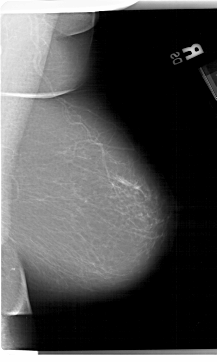

A_1275_1.RIGHT_MLO

RIGHT_MLO LINES 6871 PIXELS_PER_LINE 4111 BITS_PER_PIXEL 12 RESOLUTION 43.5 NON_OVERLAY